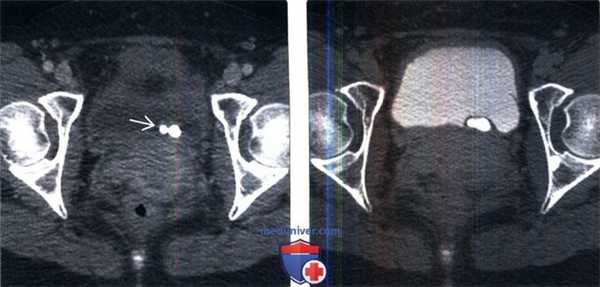

(Слева) КТ мочевого пузыря без контрастирования, аксиальный срез: два плотных кальцинированных конкремента в области левого МПС.

(Справа) Аксиальная проекция того же среза, полученная в отсроченную урографическую фазу: конкременты находятся внутри уретероцеле. Иногда дифференциальная диагностика между врожденным уретероцеле, содержащим камни и приобретенным расширением терминального отдела мочеточника при обструкции конкрементом (так называемое «певдоуретероцеле») может представлять трудность.